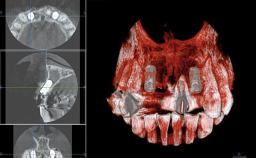

A 45-year-old woman was referred for management of an infection associated with two implant-supported crowns replacing the maxillary central incisors. Two tissue-level implants had been placed and restored with cemented single metal-ceramic crowns in those sites 4 years previously. The patient presented with a draining sinus (i.e. a pathological duct from an abscess cavity to a surface) 3 mm from the midfacial peri-implant mucosal margin of the maxillary right implant crown. She was in good general health, did not smoke, showed a good oral hygiene status, and had no history of periodontal disease. The implants were well positioned. While the patient was very satisfied with the appearance of her crowns, she had noted that the peri-implant soft tissue had receded since their insertion and was concerned about the possibility of further recession.

| # of Teeth | 2 |

| # of Implants | 2 |